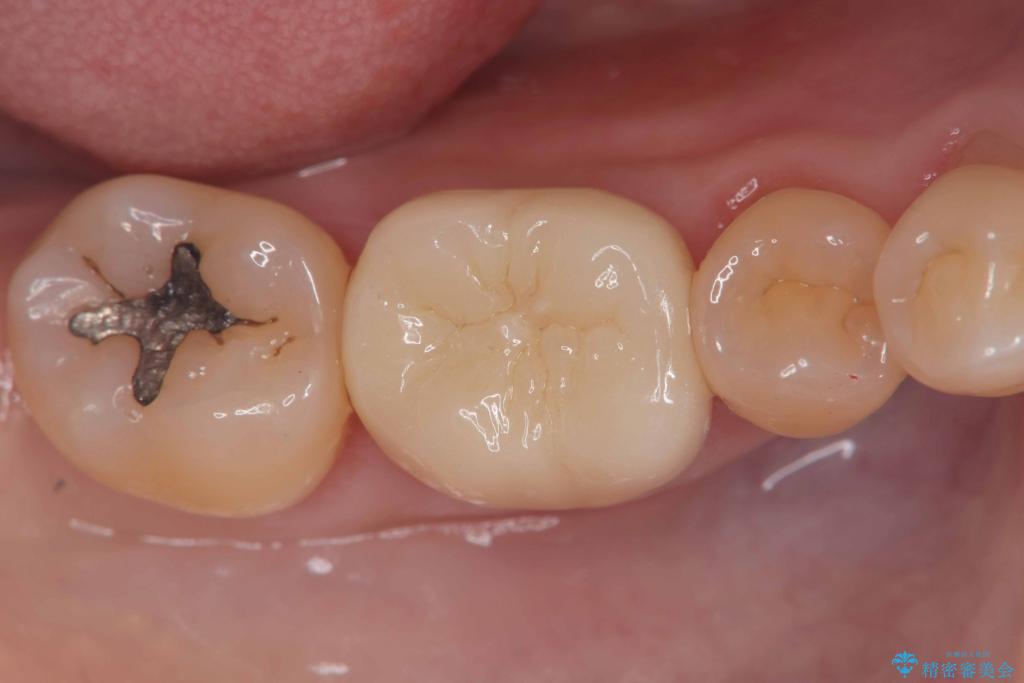

- 「銀歯を白くしたい」を主訴に来院された患者様です。銀歯を外し虫歯を除去後、オールセラミッククラウンで治療を行いました。

銀歯を外して内部の虫歯を丁寧に除去した後、オールセラミッククラウンにて修復を行いました。審美性と機能性の両面で改善が得られ、患者様にもご満足いただきました。